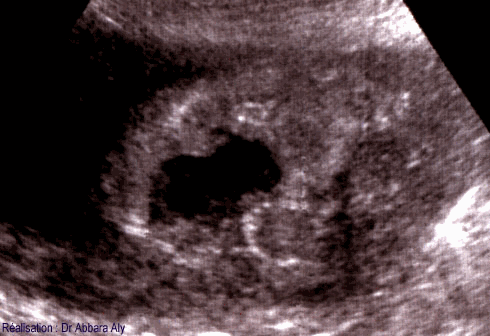

Coupe transversale du placenta montrant l'hématome rétroplacentaire

(ou le décollement prématuré du placenta) à 33 semaines d'aménorrhée